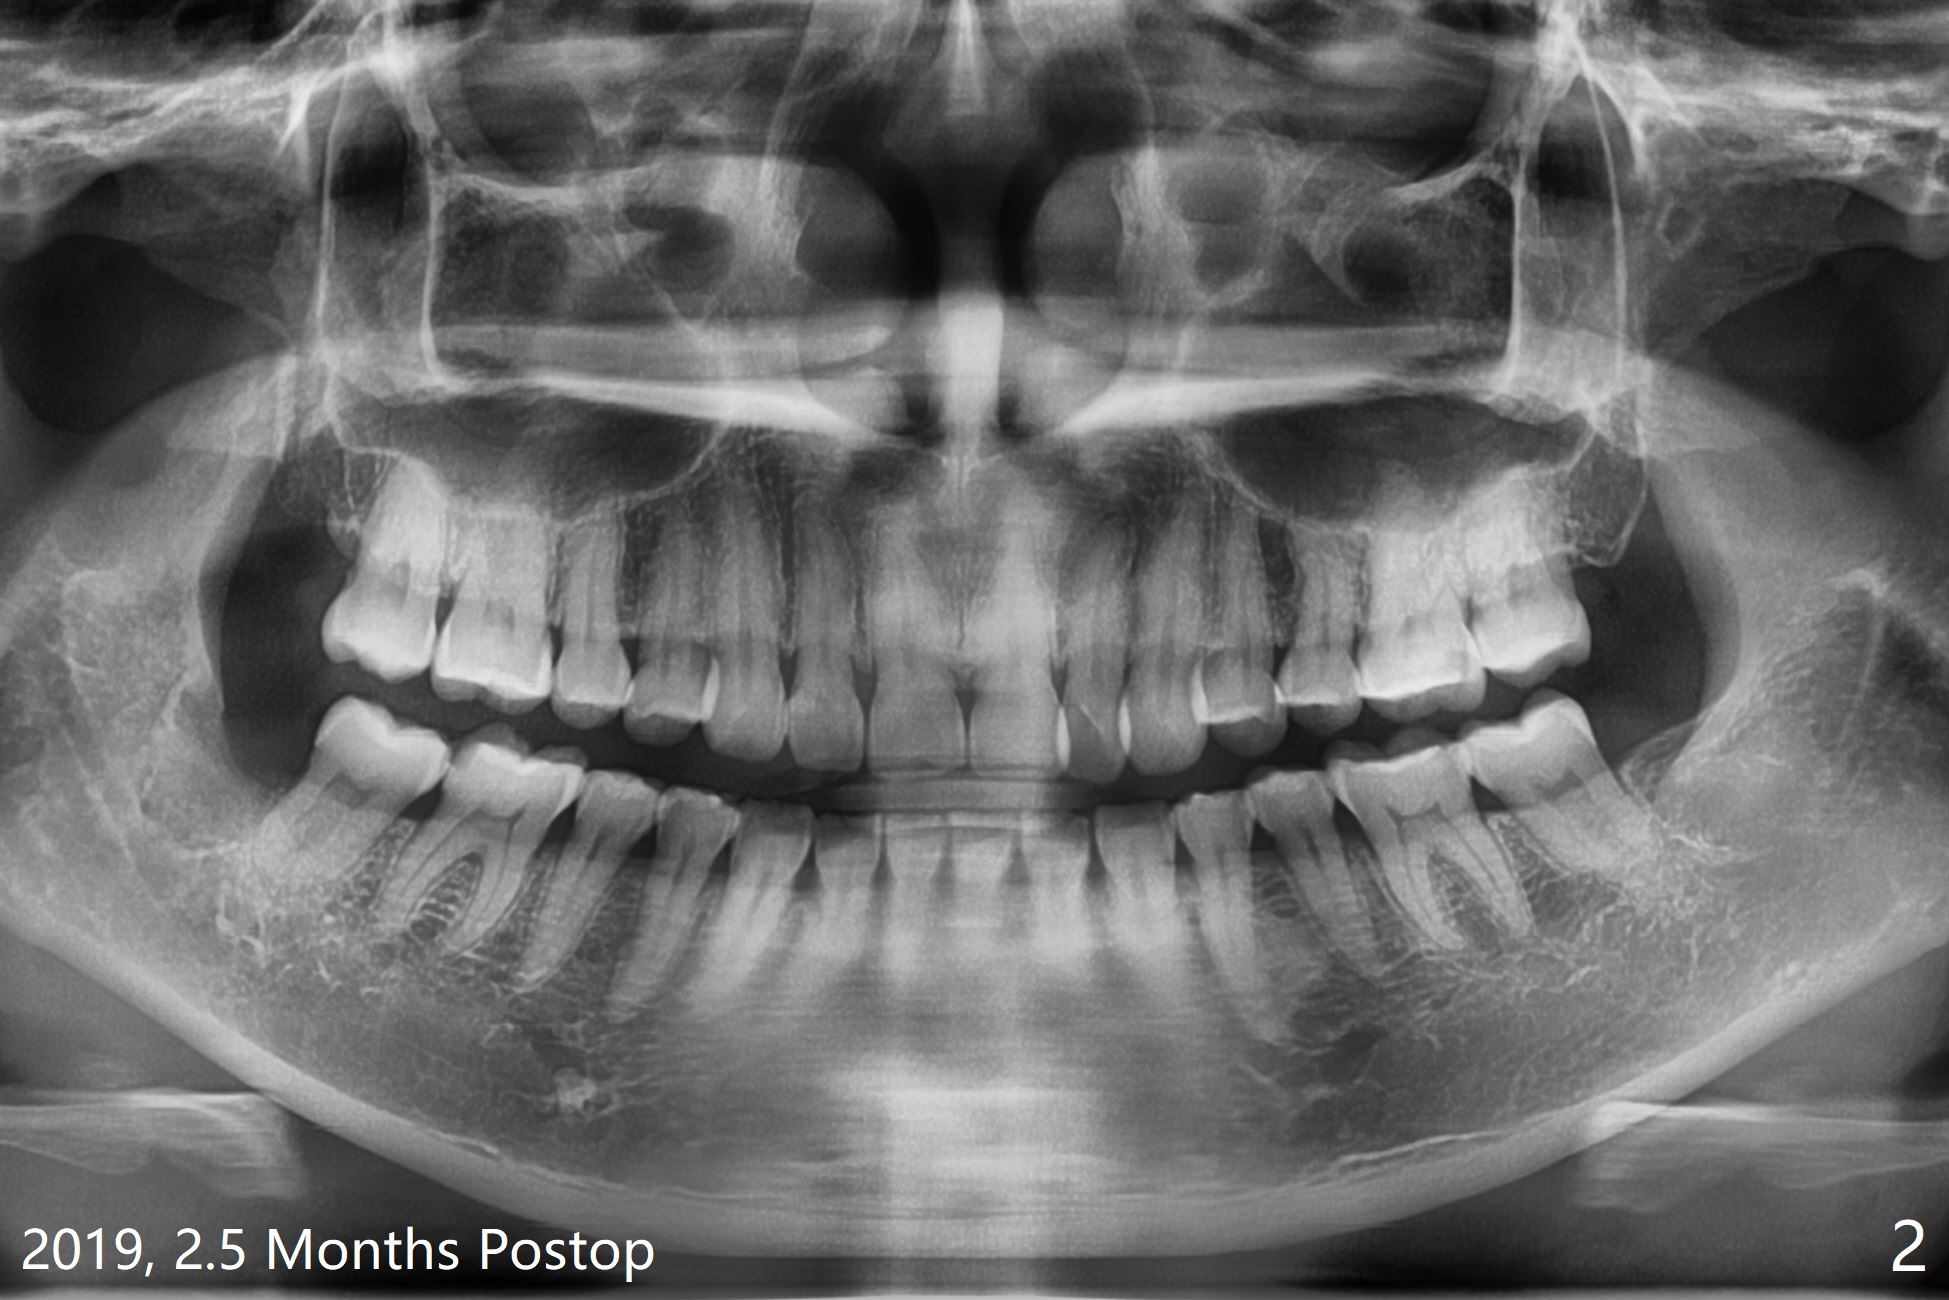

51岁女要求拔除#32(图一),劈牙两次,牙槽窝塞入胶原骨(Osteogen Plug),缝合,术后12天有不典型干槽症。术后2.5月第二,三磨牙之间牙槽嵴薄(图二:>),术后2年2个月#32牙槽窝密度高于#17(术后至少13年,图三)。